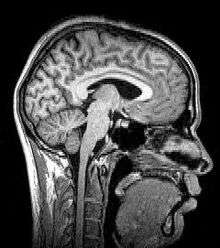

Magnetic resonance imaging

Sagittal MRI slice at the midline.

Magnetic resonance imaging (MRI) uses magnetic fields and radio waves to produce high quality two- or three-dimensional images of brain structures without use of ionizing radiation (X-rays) or radioactive tracers.